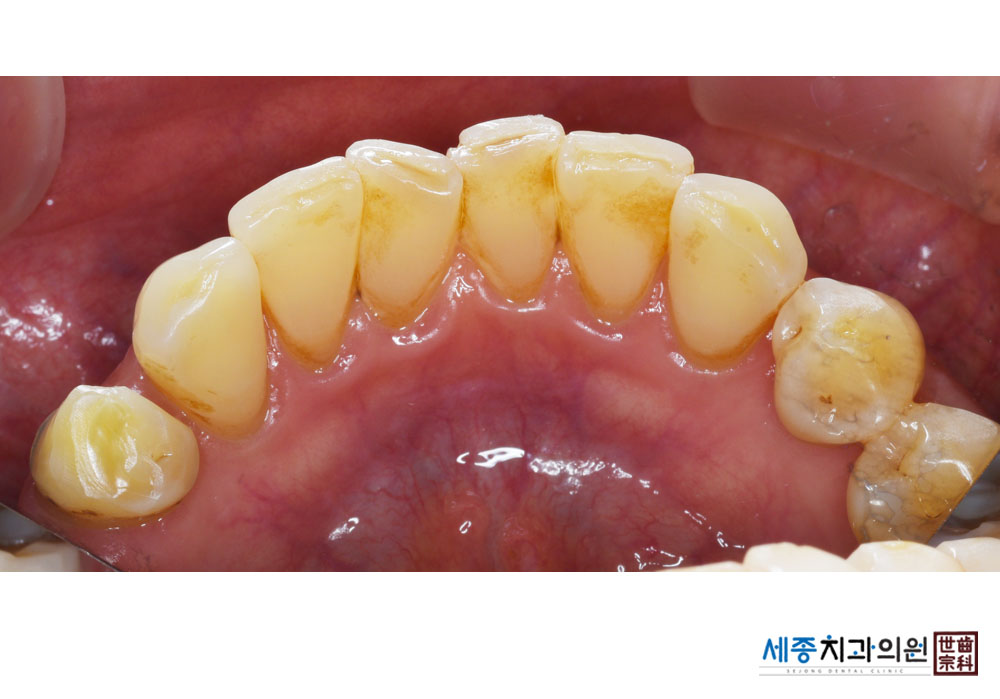

[스케일링] 치주질환 예방 스케일링

치료전 : 2021-01-14

가글마취&저주파 스켈러를 사용한 스케일링